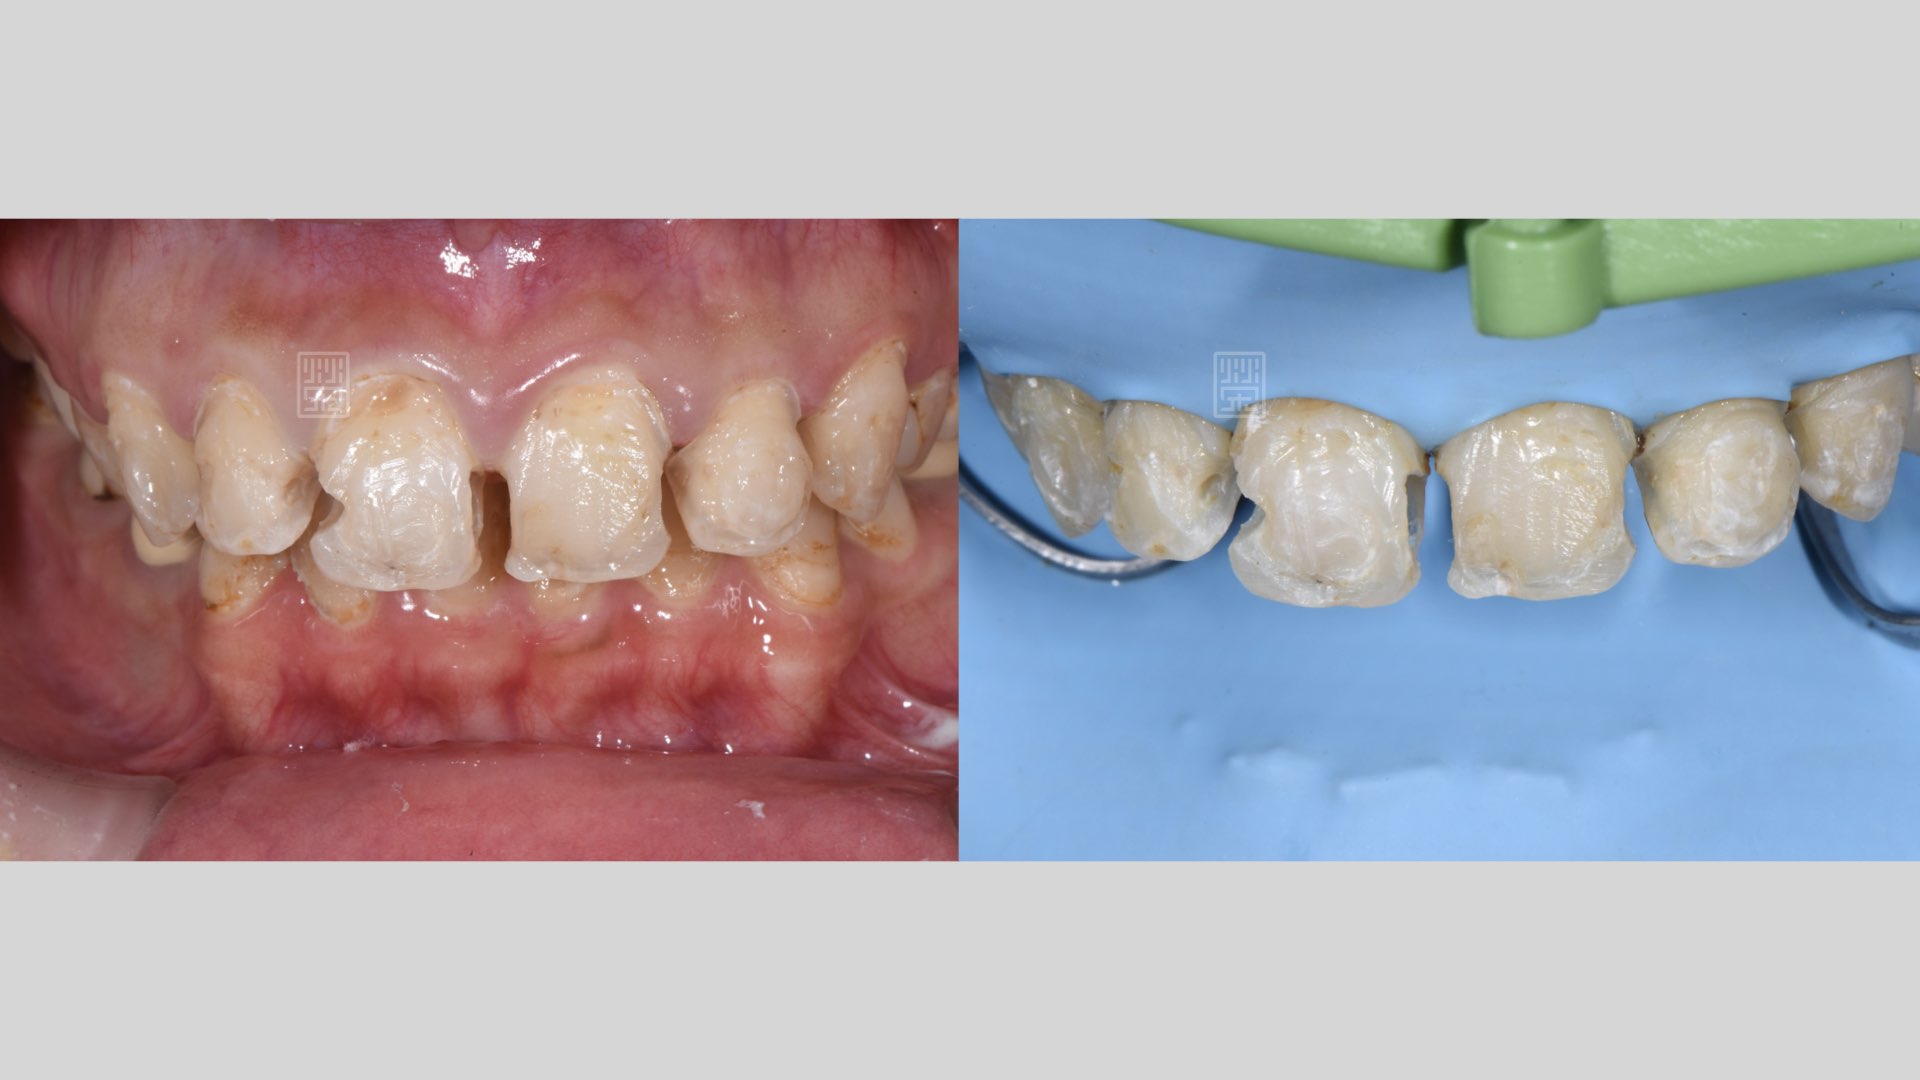

重新樹脂填補完畢

重新樹脂填補完畢,門齒比例80%,不宜做牙冠增常術